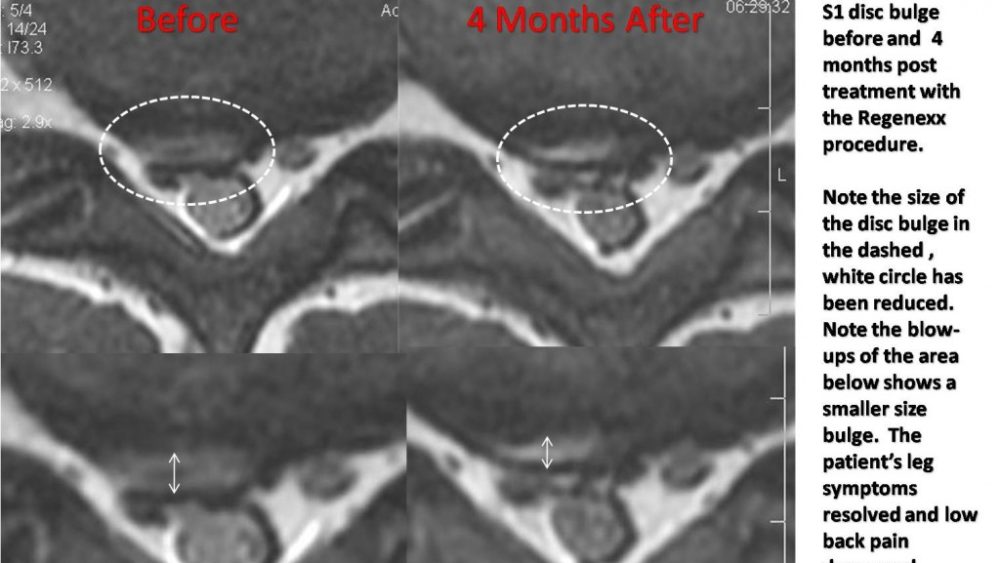

Employee Benefits or We Wouldn’t do Anything on You We Don’t Do on Ourselves